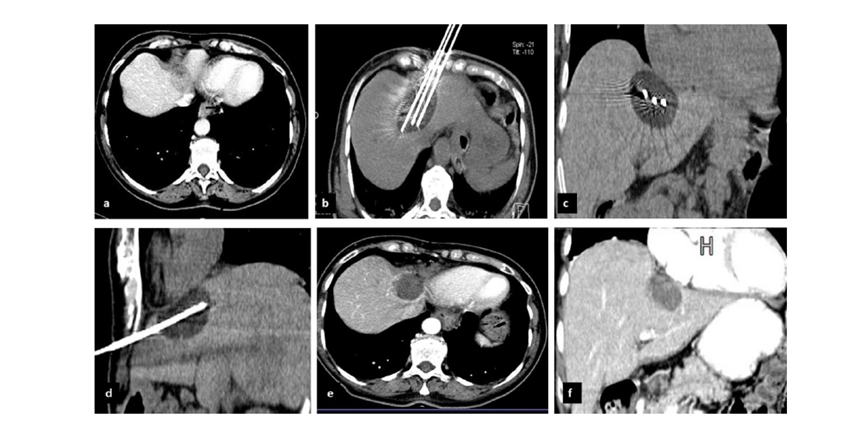

冷凍消融膽囊附近腫瘤病灶

(A)動(dòng)脈期 MRI 顯示膽囊附近有外周增強(qiáng)病變(箭頭)。

(B)手術(shù)過程中 CT 顯示冷凍探針位于病灶內(nèi)。

(C)消融后,術(shù)后 1 個(gè)月CT 顯示完全消融(箭頭)。

(A)動(dòng)脈期CT圖像顯示有一個(gè)包膜下結(jié)節(jié)(箭頭)。(B)門靜脈期CT圖像顯示病灶區(qū)(箭頭)。(C) 在手術(shù)過程中的CT顯示一個(gè)冷凍探針位于病灶內(nèi)。(D)消融后,術(shù)后1個(gè)月影像CT顯示完全消融。患者在手術(shù)及住院期間無并發(fā)癥及重大并發(fā)癥發(fā)生。隨訪時(shí)間中位數(shù)為7個(gè)月(范圍:3-12個(gè)月),隨訪期間患者無局部腫瘤進(jìn)展或死亡。

膽囊附近轉(zhuǎn)移灶(來自子宮頸癌)的冷凍消融術(shù)(A)門靜脈期 CT 圖像顯示膽囊附近有病變(箭頭)。(C) 手術(shù)過程中CT 顯示冷凍探針位于病灶內(nèi)。(D)消融手術(shù)后 1 個(gè)月CT 顯示完全消融。